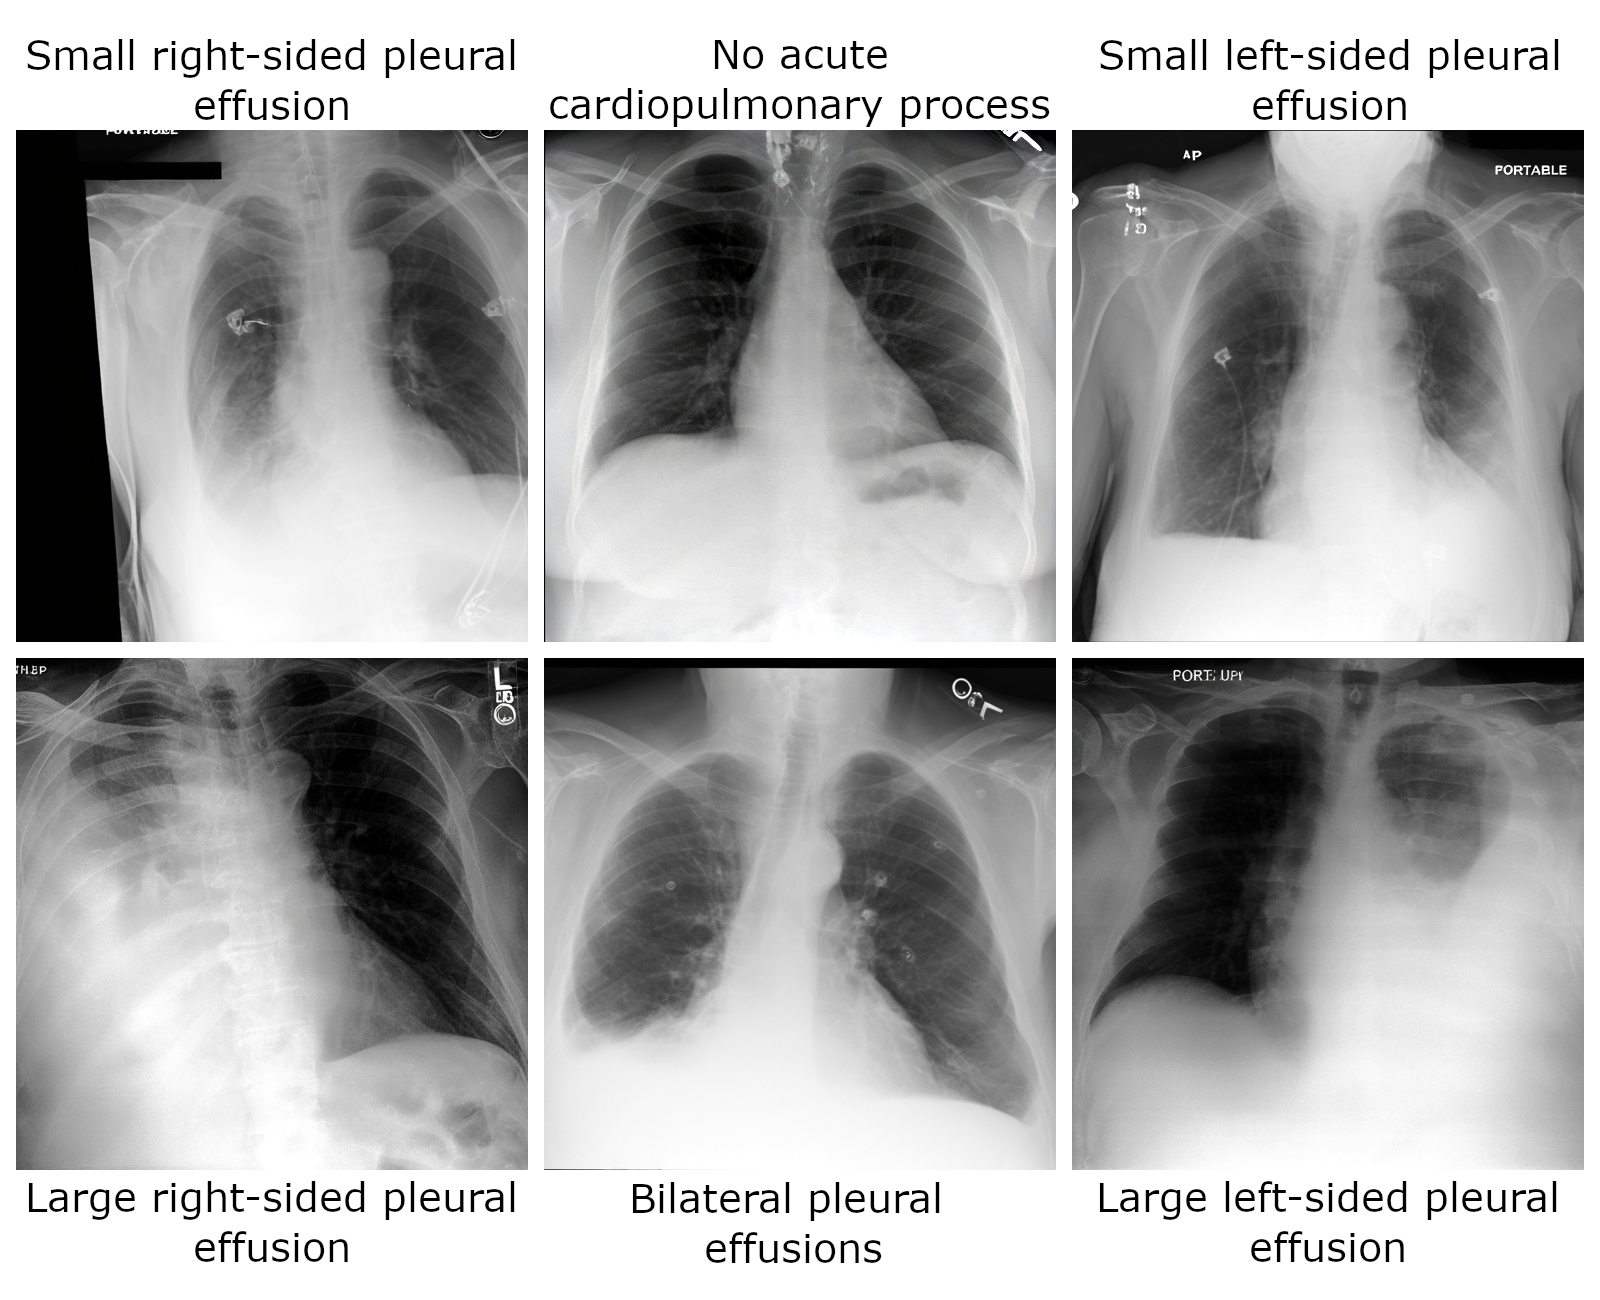

Sampling Chest X-Rays

The generation pipeline can be used to sample images via the following

prompts = [

"Small right-sided pleural effusion",

"No acute cardiopulmonary process",

"Small left-sided pleural effusion",

"Large right-sided pleural effusion",

"Bilateral pleural effusions",

"Large left-sided pleural effusion",

]

torch.manual_seed(0)

images = generation_pipeline(

prompts,

num_inference_steps=100,

guidance_scale=7.5,

).images

RadEdit Samples